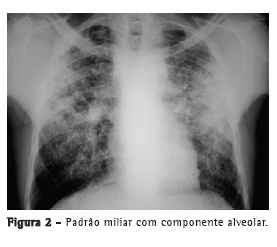

Com relação aos achados radiológicos, infiltrados reticulares e consolidação são os padrões mais frequentes,(5,6,10,15,17) sendo que cavitação pode estar presente em 27-50% dos casos.(6,10,16) As Figuras 1 a 4 mostram alguns dos principais padrões radiológicos nesse contexto.

A principal causa de internação em UTI foi a insuficiência respiratória, e o escore Acute Physiology and Chronic Health Evaluation II (APACHE II) variou de 13 a 23 na maioria dos estudos.(5,6,10,15,17) Alguns autores avaliaram os fatores associados ao desenvolvimento de insuficiência respiratória e necessidade de VM. Pneumonia ou sepse por germes gram-negativos, DPOC, história de tratamento irregular para tuberculose e neoplasia foram fatores preditores de insuficiência respiratória.(9) Em uma série de 13 casos, 7 e 6 pacientes, respectivamente, apresentavam tuberculose miliar/disseminada e pneumonia tuberculosa, necessitando cuidados intensivos. Comparados com os pacientes com pneumonia tuberculosa, os pacientes com tuberculose miliar/disseminada foram mais propensos a necessitar VM (18,9% vs. 0,8%; p < 0,0001).(8)

O tempo entre o início dos sintomas e o início do tratamento antituberculose descrito nos estudos foi maior do que 30 dias em 28,8-34,0% dos casos.(6,17) O tempo entre a admissão e o início da terapêutica adequada foi avaliado em apenas um estudo, sendo relatada uma média de 4,3 dias. Naquele estudo retrospectivo, o tempo entre a admissão e o início do tratamento foi menor nos pacientes com tuberculose miliar do que naqueles com pneumonia tuberculosa (2,8 ± 2,5 dias vs. 5,0 ± 7,0 dias; p = 0,048).(16) Pode haver atraso no diagnóstico e, consequentemente, no começo do tratamento pela difícil diferenciação radiológica entre pneumonia tuberculosa e pneumonia bacteriana grave. Considerando essa dificuldade na distinção entre as duas patologias, um estudo avaliou as diferenças nas características clínicas e radiológicas de pacientes com pneumonia grave com e sem tuberculose internados em UTIs. A história de sintomas com duração maior do que duas semanas e a presença de micronódulos ou de padrão cavitário na radiografia de tórax foram significativamente associados com tuberculose pulmonar ativa.(20) Adicionalmente, o padrão miliar na radiografia de tórax também pode ser erroneamente interpretado como insuficiência cardíaca congestiva.(18)

Pelo exposto acima, o papel da radiografia de tórax no diagnóstico clínico da tuberculose pulmonar permanece incerto em pacientes em UTIs, podendo não contribuir tanto quanto o esperado. Em um estudo caso-controle, 89 pacientes com tuberculose pulmonar e um número igual de controles foram avaliados, sendo que o padrão radiológico mais comumente encontrado foi a consolidação, em 61 pacientes (6,5%). Na análise multivariada, a história de tuberculose pulmonar prévia foi associada com a suspeita clínica de tuberculose, mas os padrões radiológicos não foram associados a essa suspeita.(21)